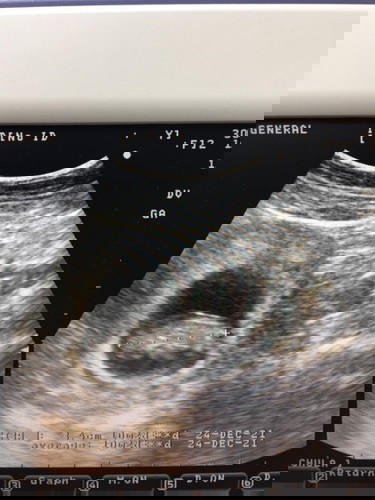

คุณแม่มือใหม่ตอนนี้ตั้งครรภ์ได้10w5dลูกนอนคว่ำหน้าอยากทราบว่าปกติเด็กนอนท่าไหนค่ะ

บ้านนี้ก็คว่ำหน้าค่ะ แต่ตอนนี้37+1 กลับหัวแล้วค่ะ เป็นเรื่องปกติค่ะ